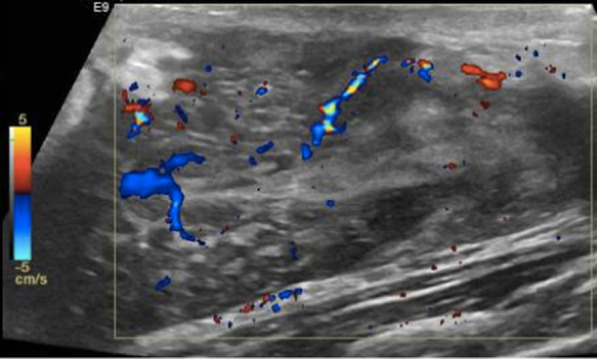

An ultrasound scan of her right breast revealed a large, complex area measuring approximately 3.3 cm in thickness with areas of internal vascularity (Fig. 2). Upon surgical consultation, needle aspiration of the right breast was performed, and the aspirate fluid was sent for bacterial, fungal, and acid fast (AFB) staining as well as culture. Sonogram guided, vacuum-assisted core biopsy revealed chronic inflammation of the breast with adjacent granulomatous inflammation with neutrophilic microabscess formation. Chest roentgenogram was negative for any mediastinal lymphadenopathy, cardiac, or pulmonary abnormalities. Ophthalmologic examination including slit lamp examination was negative for uveitis and episcleritis. Based on lack of these systemic findings, the diagnosis of idiopathic granulomatous mastitis with erythema nodosum and polyarthritis was made.

Fig. 2.

Doppler ultrasound of the patient’s right breast revealed a large, complex area measuring approximately 3.3 cm in thickness with areas of internal vascularity